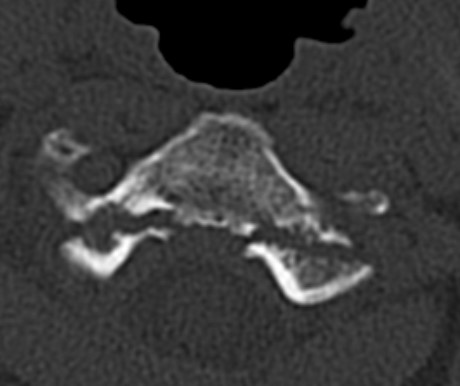

Bilateral pars fracture of C2

Traumatic spondylolisthesis of C2

CT scan